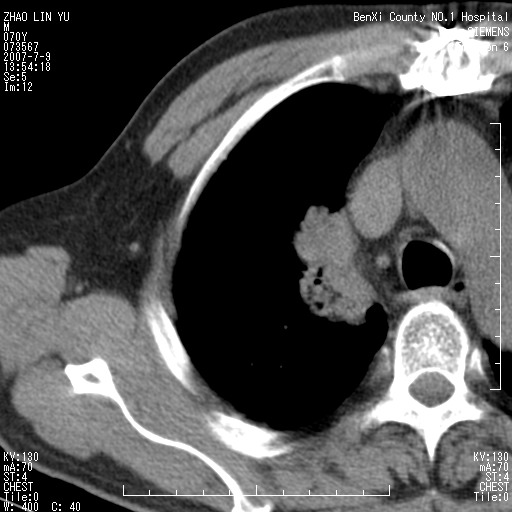

以下是引用王靖旗在2007-7-10 17:12:00的发言:[br] 男、70、咳嗽两个月,半年前换瓣手术,胸片未见异常,于昨天行x片发现右肺上野大片影,行ct扫描,这里是减薄图像,余肺正常。明天晚上会有增强扫描片,到时我会上传。[br][br] 冠状位请大家细看,应该是有意义的,[br][br] 请大家先看平扫发表意见。[br][br]

以下是引用zhangzhongshou在2007-7-10 21:43:00的发言:[br]右肺上叶周围型肺癌,以孤立型细支气管肺泡癌可能性大。